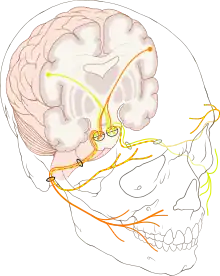

Nervul facial (latină Nervus facialis) este cel de-al șaptelea nerv cranian și este un nerv mixt (motor, senzorial, vegetativă parasimpatică). Controlează mișcările mușchilor mimicii (ai expresiei faciale), trimite informații senzoriale legate de gust (două treimi de pe mucoasa linguală anterioară). De asemenea, conține fibre vegetative parasimpatice, inervând glandele lacrimale și salivare (submandibulare și sublinguale). [1][2]

Nervul facial are originea aparentă în șanțul bulbopontin și originea reală în: ganglionul geniculat (pentru calea senzorială), nucleul motor din punte (pentru calea motorie) și nucleul lacrimal și salivator superior (pentru calea vegetativă parasimpatică). [3] [1]